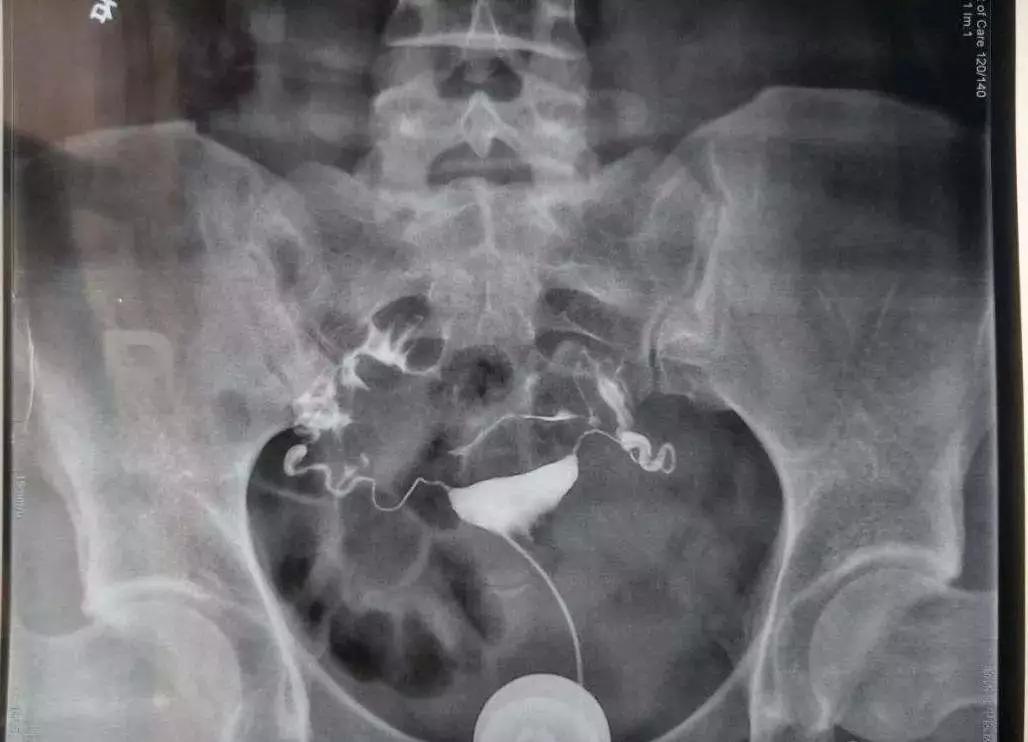

对于不孕症患者,可通过输卵管通液、子宫输卵管造影、宫腹腔镜下输卵管通液术等检查。临床上,首先推荐行子宫输卵管造影。此检查可分类近端或远端堵塞,或通而不畅等,可以为后续治疗方案提供一定参考价值。